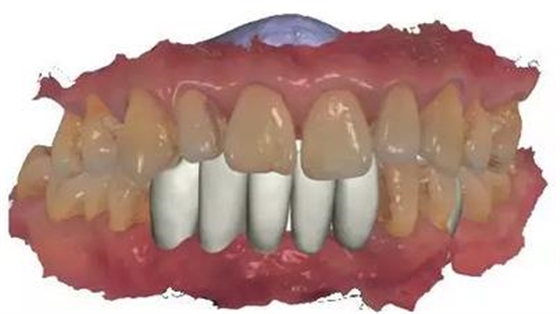

通過3shape trios口內(nèi)掃描儀掃描數(shù)據(jù)。

通過3Shape Dental System軟件同期設(shè)計(jì)臨時(shí)冠